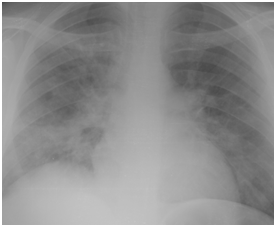

Figure 4A Chest X-ray film on day two from suffering attack of low grade fever.

Figure 4B Follow up Chest X-ray at time of diagnosing H1N1 pneumonia 6 days later.

Figure 4 H1N1 radiological pictures in a diabetic 28-year-old transplant recipient.